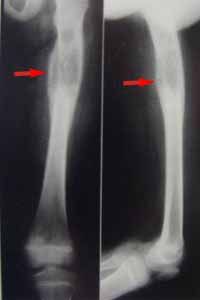

惡性組織細胞病(malignanthistiocytosiv)簡稱惡組,是組織細胞系的一種惡性增生性疾病。多見於成人和青壯年,但小兒時期也可發生少數病例。其主要的病理特點是肝、脾、淋巴結、骨髓等器官、組織中出現廣泛的惡性組織細胞或分化較高的組織細胞灶性浸潤,並伴有明顯的血細胞被吞噬現象。

任何年齡均可患病,以15~40歲占多數,男女之比約為3∶1,以農民為多見。臨床表現可分為急性型和慢性型(病程在1年以上)兩種,以急性型為多。起病急驟,病程短促、兇險,發熱為首見及常見的症狀(97.2%),多為持續高熱,少數為不規則發熱,而隨病程進展而漸升高。少數也可以乏力、上呼吸道感染或肝、脾、淋巴結腫大起病。總之病情進展迅速,短期內明顯消瘦,極度衰弱。由於骨髓被大量異常組織細胞浸潤及組織細胞有吞噬血細胞的作用,加上脾亢及毒素抑制等作用,大多數患者有全血細胞減少。

異常組織細胞(二)骨髓檢查多數增生活躍,增生低下病例多已達晚期。多數病例骨髓中能找到多少不一的異常組織細胞:

③吞噬型組織細胞:其形態與正常所見巨噬細胞類同,漿內常吞噬大量血細胞,包括幼紅細胞、成熟紅細胞殘片、血小板,偶有少數中幼粒細胞。此外,尚可見淋巴樣、單核樣、早幼粒樣、漿細胞樣及異常核絲分裂型組織細胞,其中異形組織細胞和(或)多核巨組織細胞對惡組有診斷意義。吞噬型、淋巴樣和單核樣組織細胞在其它疾病中都可出現,因此沒有特異性診斷價值。由於骨髓受累程度不一致,病灶分布不均勻,因此一次骨髓穿刺陰性者,不能排除診斷,反覆多部位穿刺可提高診斷的陽性率。骨髓活檢或骨髓液凝塊檢查也可提高本病診斷陽性率。